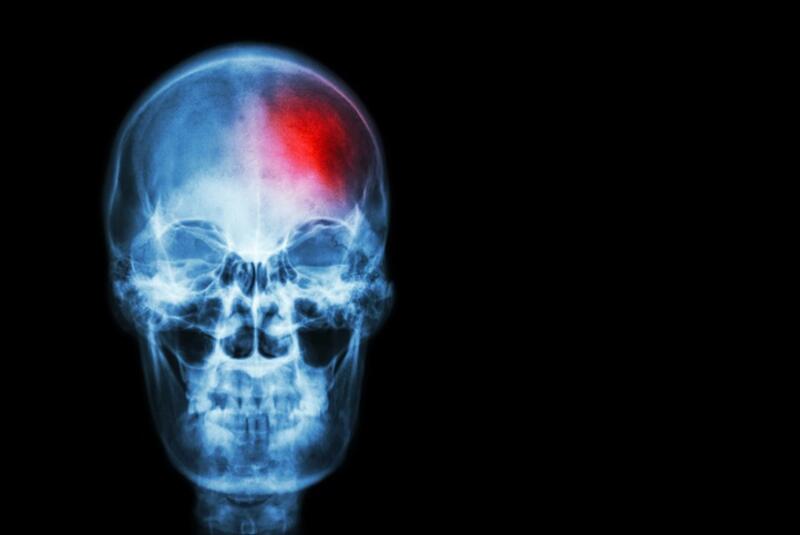

Aunque la presión arterial alta o hipertensión ha sido un factor de riesgo bien establecido para el ictus y para las muertes, tener la presión arterial baja es un factor de riesgo igual de grande para la muerte después de un ictus, según un estudio de la Boston University School of Medicine (Estados Unidos).